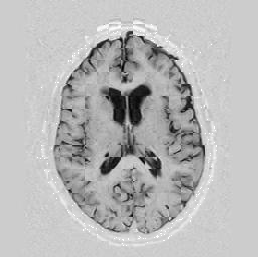

Another larger group of experiments enabled me to study the effects of multi-scale NRR. The results are shown in the form of chequerboard images in Figure [*]. In terms of resolution levels, higher numbers mean that the images are coarser.

Judging by some later stages when resolution is increased, the conclusion reached is that the added computational effort, which is enormous, makes this increase unneeded. The increase in resolution does not reveal much new information about the image structure, at least not at the stage when registration is still far from being entirely approached.

Figure: Multi-scale NRR (increasing resolution). From left to right, top then bottom:before NRR; after 5 iterations of NRR at level 2 (higher is coarser); after another 5 iterations of NRR at level 1.

The results are shown for another pair of images in Figure [*].

Figure: Multi-scale NRR. From left to right, top then bottom: before NRR; after 5 iterations of NRR at level 2; after another 5 iterations of NRR at level 1.